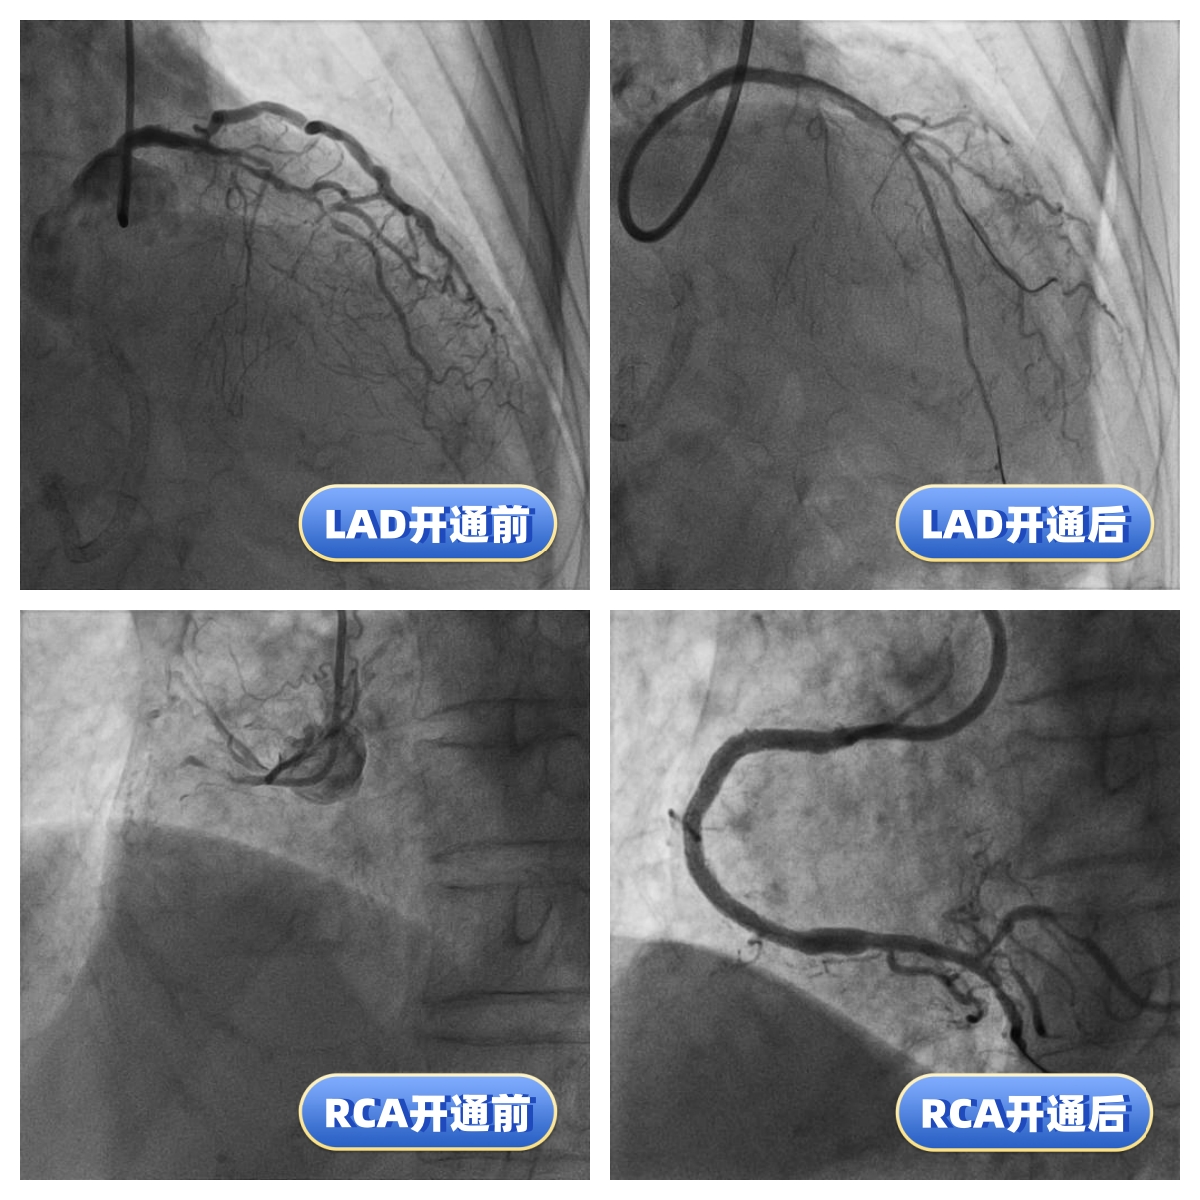

今年83岁高龄的刘老先生,退休前从事地质工作,平素身体硬朗,但近期发现快走后出现憋气症状,到某医院就诊,冠状动脉造影检查为三支病变,前降支(LAD)、回旋支(LCX)、右冠状动脉(RCA)均为完全闭塞病变且伴重度钙化。患者辗转两家医院,两次尝试血管开通均未成功。医院告知患者家属,冠状动脉搭桥术是唯一的出路。但是搭桥手术对于一位83岁高龄的老人来说无疑是一个艰难巨大的挑战。两次失败手术的打击使得刘老先生的身体状态每况愈下,稍事活动就气喘吁吁,逐渐对生活失去了信心。后来家属打听到附属北京潞河医院心内科翟光耀主任团队致力于冠状动脉复杂手术,抱着最后一搏的想法,刘老先生再次躺在了手术台上。术中,冠状动脉造影结果让翟光耀主任团队意识到了这次手术的难度之大,风险之高。三支主干闭塞,之前手术开通失败已造成血管近端夹层,闭塞的血管(尤其是RCA)全程重度钙化,近乎全程闭塞,开通血管无疑在花岗岩上开凿隧道。在近4个小时的不懈努力后,团队终于成功开通了难度最大的RCA并植入支架,观察一天后顺利出院。一个月后,刘老先生闭塞的LAD也成功开通。现在,刘老先生身体恢复良好,如获新生!